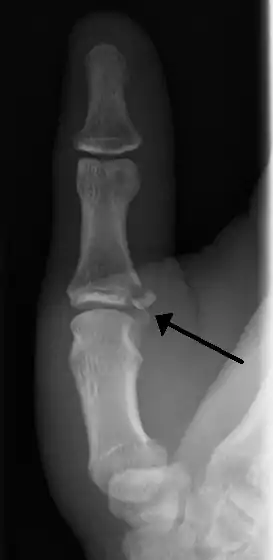

| Avulsion fractures of the ulnar base of the proximal phalanx of the thumb ( Gamekeeper's fracture ) | |